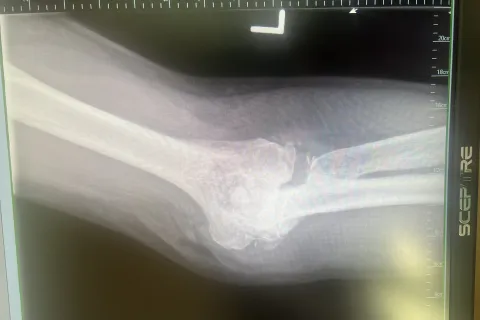

Carrell Clinic and Dr. Worrel took great care of me. Very prompt appointment and service every time. My left elbow replacement surgery was professional and went without any issues. Recovery is extensive but expected. My ulnar nerve along with my elbow was in bad condition. Joint was shattered and removed in 1998, but is better after surgery than it ever has been in 30 years. Amazed!!

I was told over the years that technology was not available for elbow replacement. It is now!